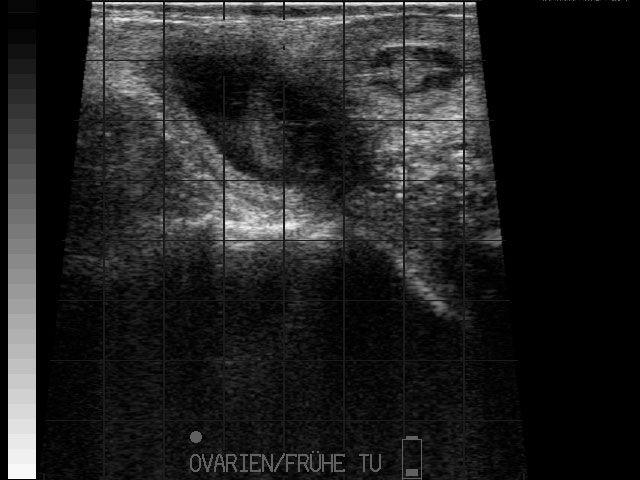

Eierstockstumor